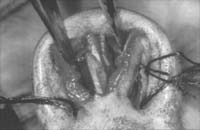

Figure 1. Plumping grafts may improve a retracted columella.

Plumping grafts may he used to open up an acute nasolabial angle, improve a retracted columella, and support a deficient nasal base. Dissect a midcolumellar precise pocket to just above the nasal spine. Place multiple small pieces of cartilage (I mm to 2 mm), harvested from the septum or ear, in the pocket. These grafts will augment the deficient area (Fig. 1) (1,2). Plumping grafts placed below the medial crural footplates will increase sup-port of the nasal base (Appendix F)